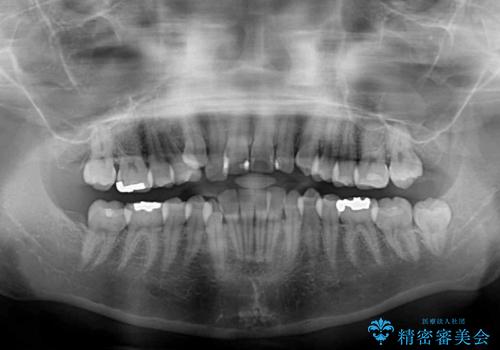

八重歯の後ろの歯を1歯抜歯し、補助装置(リンガルアーチ)を用いて八重歯の位置を改善し、その後インビザラインにより矯正治療を行うこととしました。

右側のみ上下小臼歯を抜歯したため、上下の正中が右にずれてしまう可能性があります。

また、元々右側は上下が咬み合っていないため、矯正をしても咬み合わないことも考えられました。

治療期間はかかりましたが、正中も合い、綺麗な仕上がりとなりました。